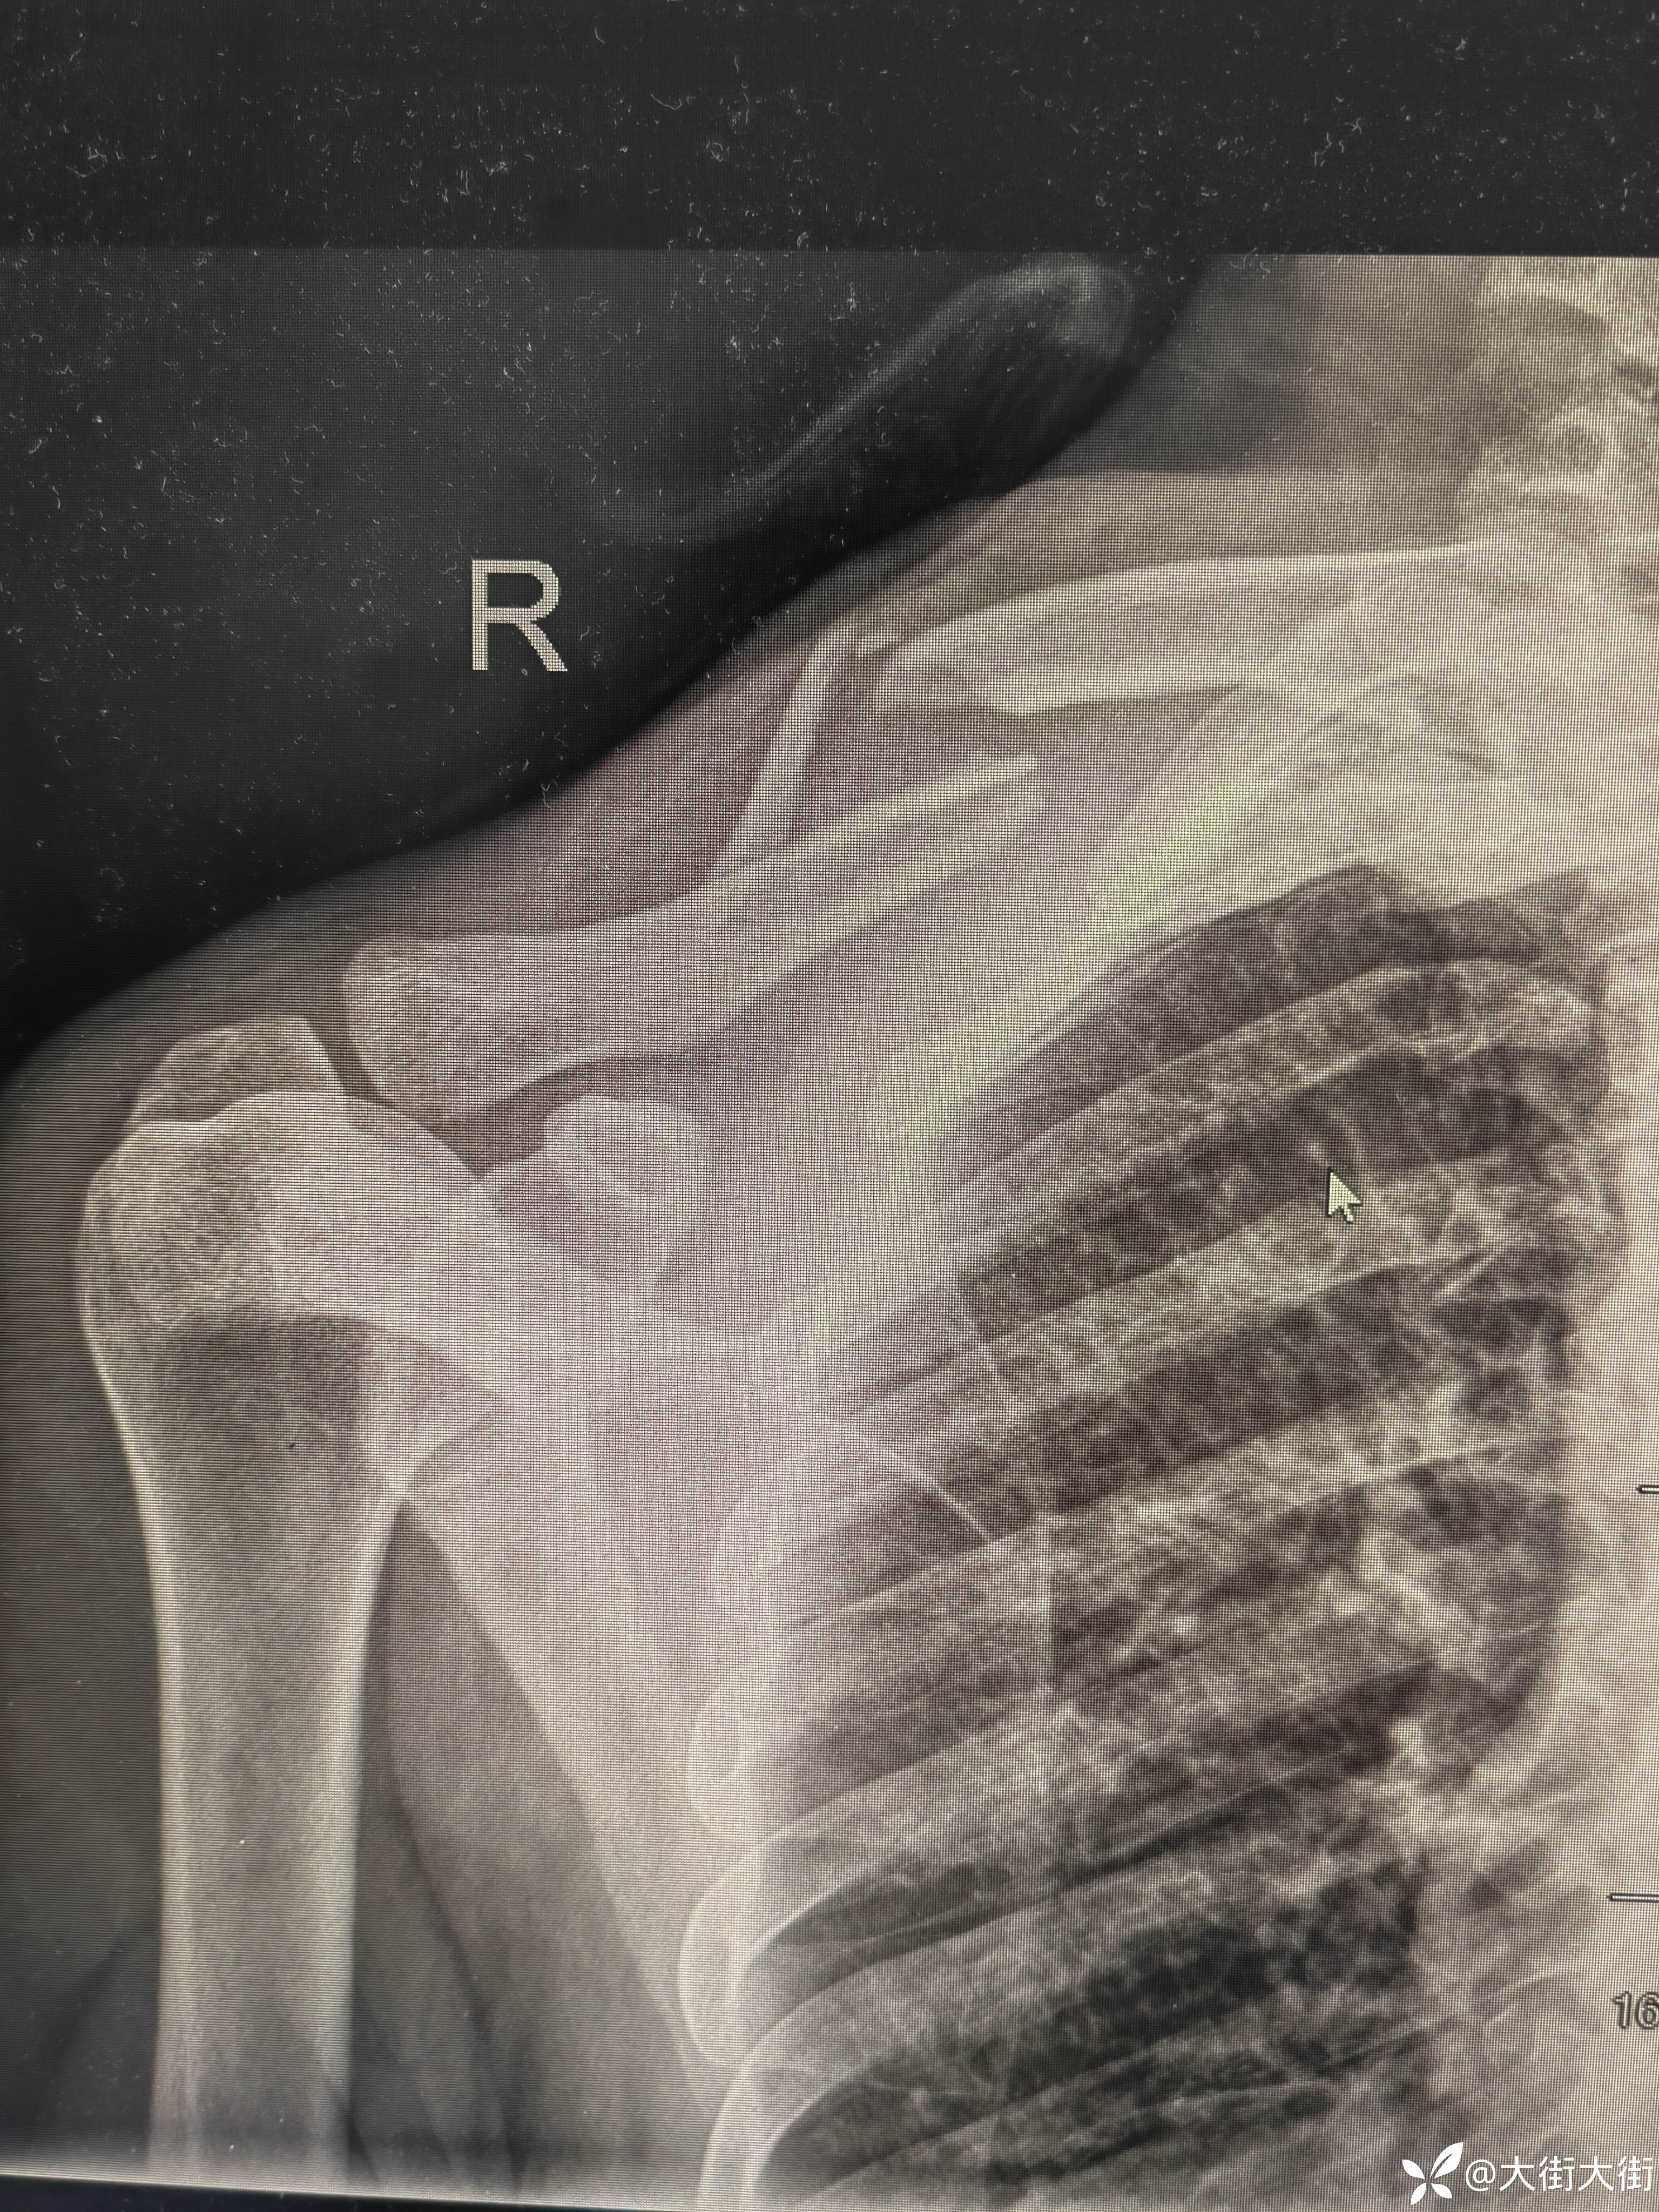

【患者信息】:男,61岁

【主诉】:外伤致右肩部疼痛,活动受限3天。

【临床诊断】: